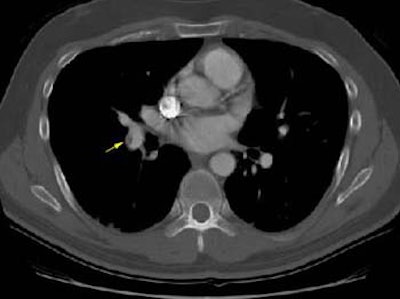

CT scan revealed eccentric thrombus in the right lower lobe pulmonary artery: